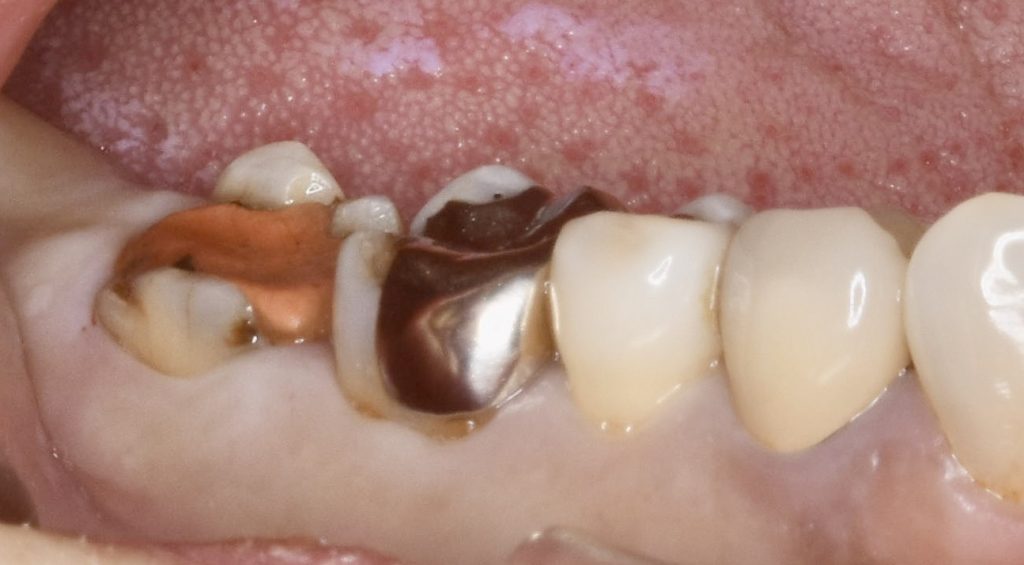

今回、古いメタルインレーの中でカリエスが進行し、骨縁下まで進行していました。

抜歯と同時にインプラント埋入手術を行い、4ヶ月ほどで治療を完了いたしました。